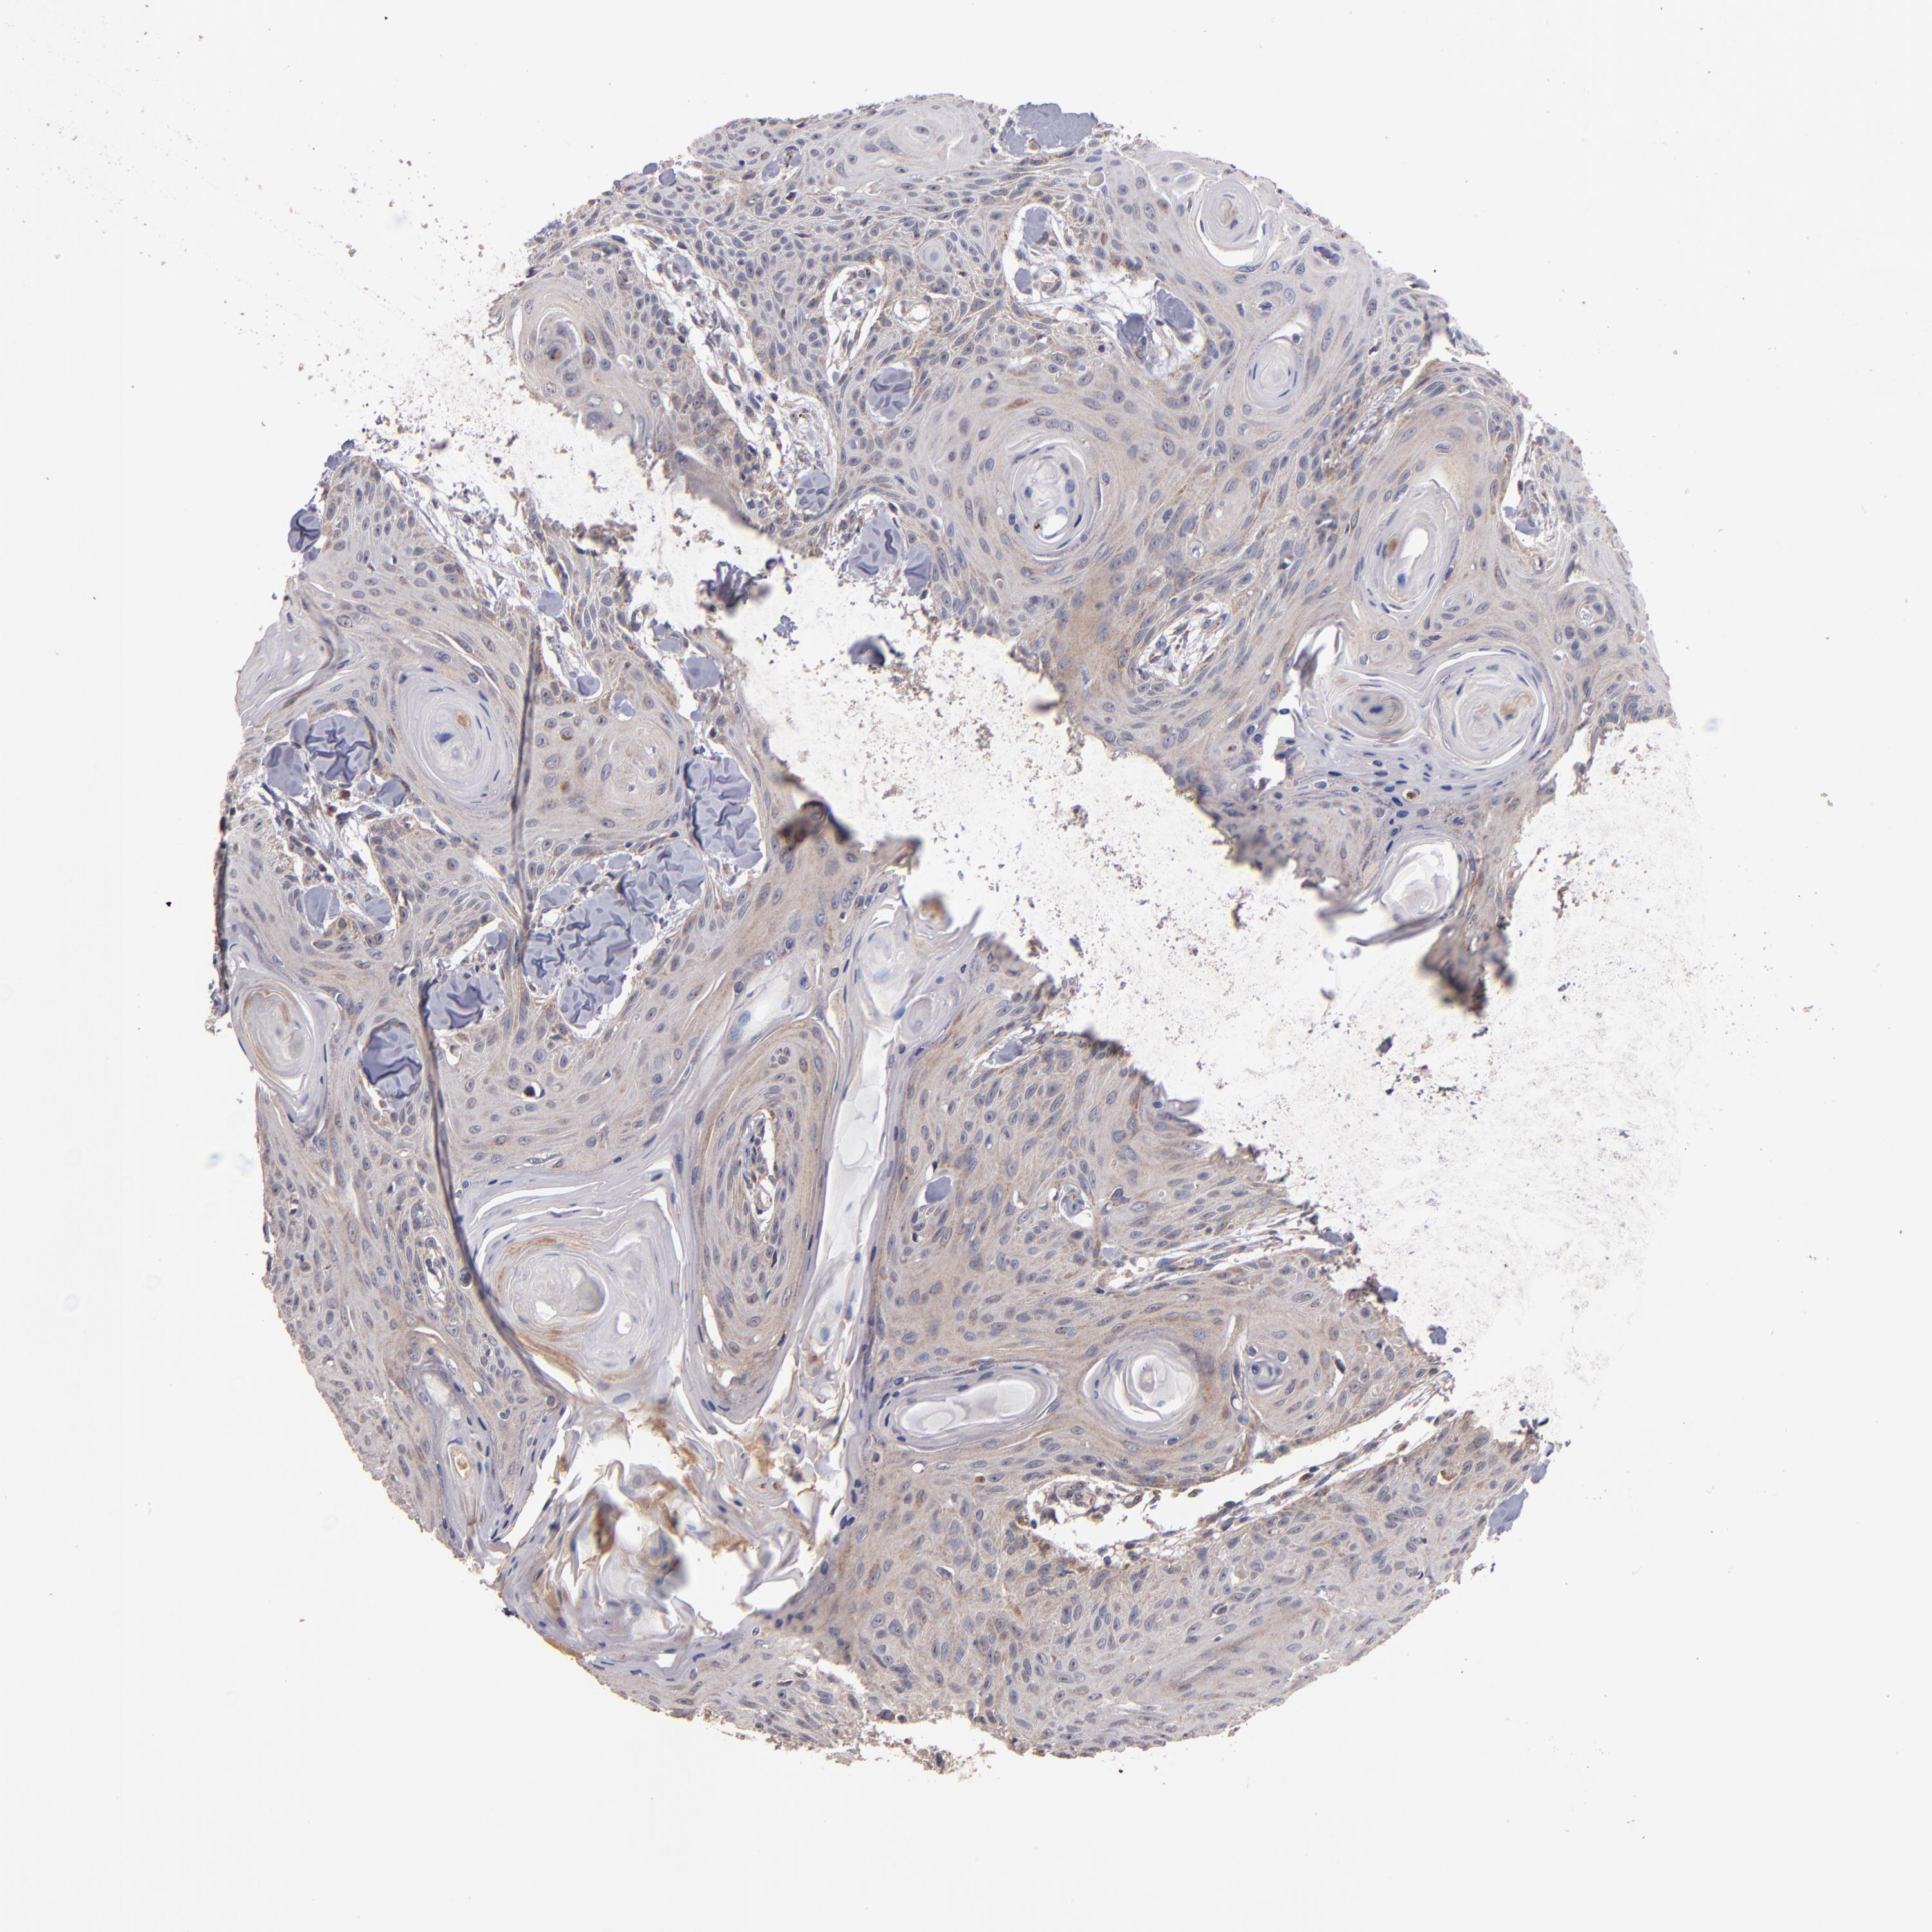

HEAD AND NECK CANCER - Protein expressioni

A mouse-over function shows sample information and annotation data. Click on an image to view it in a full screen mode. Samples can be filtered based on level of antibody staining by selecting one or several of the following categories: high, medium, low and not detected. The assay and annotation is described here.

Antibody stainingi

Antibody staining in the annotated cell types in the current human tissue is reported as not detected, low, medium, or high, based on conventional immunohistochemistry profiling in selected tissues. This score is based on the combination of the staining intensity and fraction of stained cells.

Each image is clickable and will lead to virtual microscopy that enables deeper exploration of all samples and also displays staining intensity scores, fraction scores and subcellular localization as well as patient and tissue information for each sample.

Antibody HPA001825

Staining

High

Medium

Low

Not detected

Intensity

Strong

Moderate

Weak

Negative

Quantity

>75%

75%-25%

<25%

None

Location

Nuclear

Cytoplasmic/membranous

Cytoplasmic/membranous,nuclear

Squamous cell carcinoma, NOS